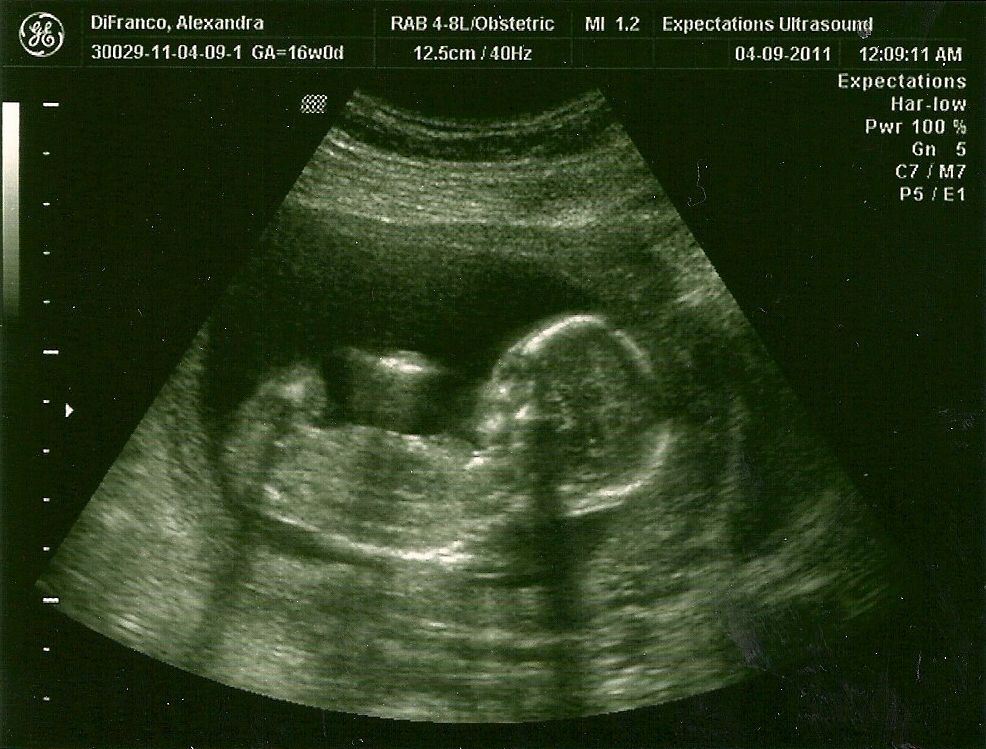

Медицинские Факты: Омфалоцеле на 12 Неделе Беременности

Раздел: Снимки мастерства